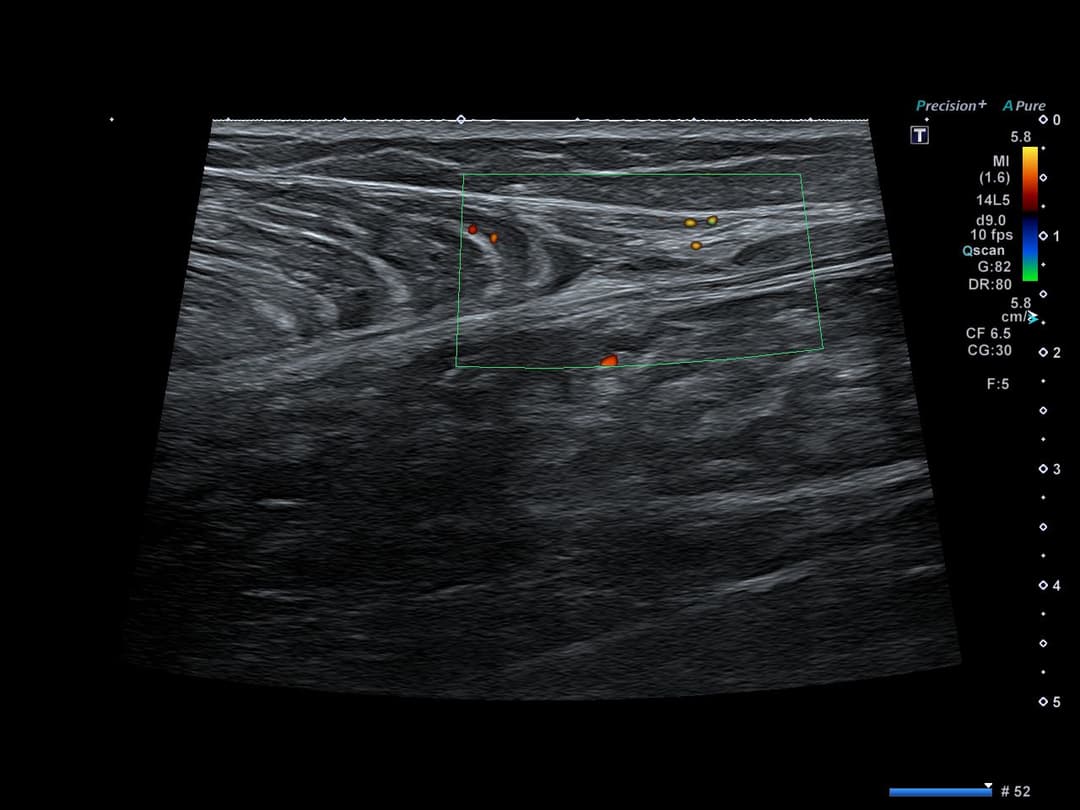

Bilan lésionnel initial montrant une rupture de la continuité du prolongement aponévrotique libre du muscle gastrocnémien médial